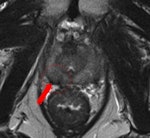

A 69-year-old male three years post electron-beam radiation therapy (EBRT, primary PC: Gleason 4+3 right PZ) with PSA increase to 2. MRI and TRUS-guided biopsy of this area confirmed Gleason 4+4 recurrence at right PZ (old tumor location). Left: Axial T2-weighted MR image shows low signal prostate due to previous EBRT. Therefore, tumor (arrow) is difficult to see. At arrow, there is some "bulging" (PI-RADS 5). Center: Axial DCE-MRI shows increased focal asymmetric contrast leakage at right PZ (circle, PI-RADS 5). Right: Axial ADC-map of DWI-MRI shows restriction (low signal, circle, PI-RADS 5). Final diagnosis: PI-RADS 5. TRUS biopsy of this area confirmed Gleason 4+4 recurrence.

A 69-year-old male three years post electron-beam radiation therapy (EBRT, primary PC: Gleason 4+3 right PZ) with PSA increase to 2. MRI and TRUS-guided biopsy of this area confirmed Gleason 4+4 recurrence at right PZ (old tumor location). Left: Axial T2-weighted MR image shows low signal prostate due to previous EBRT. Therefore, tumor (arrow) is difficult to see. At arrow, there is some "bulging" (PI-RADS 5). Center: Axial DCE-MRI shows increased focal asymmetric contrast leakage at right PZ (circle, PI-RADS 5). Right: Axial ADC-map of DWI-MRI shows restriction (low signal, circle, PI-RADS 5). Final diagnosis: PI-RADS 5. TRUS biopsy of this area confirmed Gleason 4+4 recurrence."Prostate imaging at 3-tesla benefits from higher signal-to-noise ratio and enables high-quality imaging within a short time without the use of an ERC [endorectal coil]. Data on 3-tesla for prostate cancer MRI are still conflicting. Thus, further research on this topic is needed," the authors noted. "Limitations of 3-tesla MRI are shorter T2- and longer T1-relaxation times, problems with susceptibility artifacts, dielectric effect, specific absorption rate, and the homogeneity of the magnetic field. However, hardware, multichannel coil, and parallel imaging technique improvements are currently solving most of these problems."